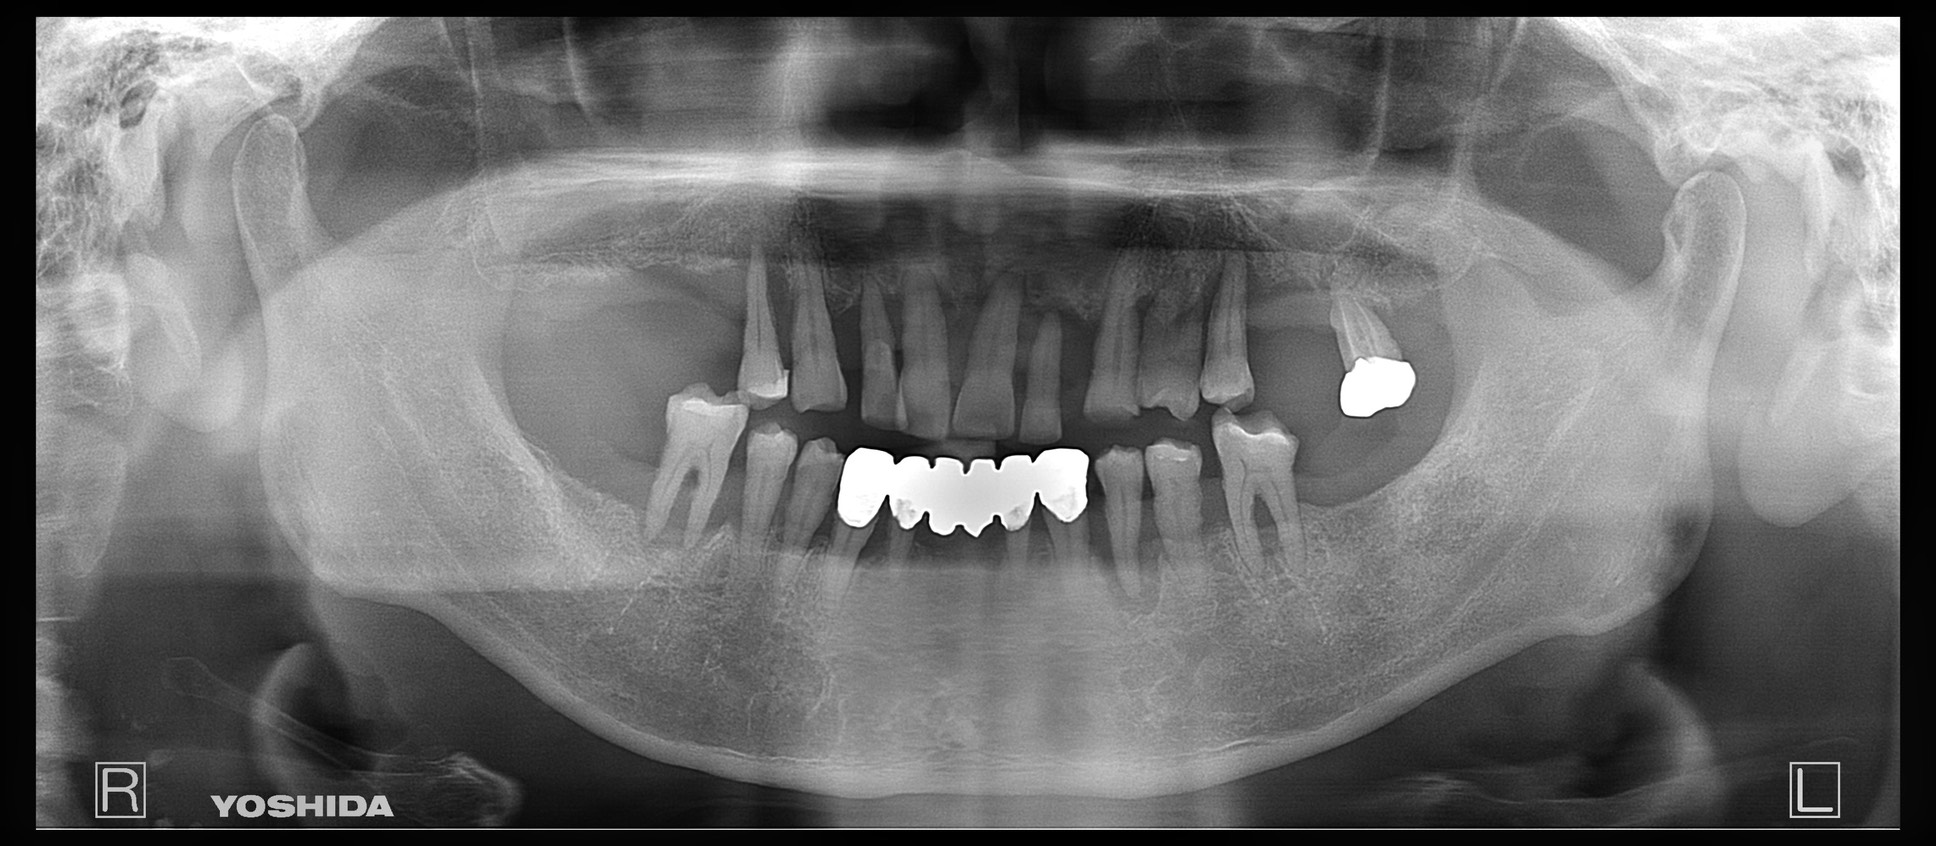

残存歯を抜歯後、上顎は4本、下顎は2本インプラントを埋入しました。

インプラントが顎骨と結合した後、IODを作成しました。

完成した義歯が以下です。

義歯の穴が空いてる部分にマグネットを埋め込んでます。今回は金属床義歯で作製してます。